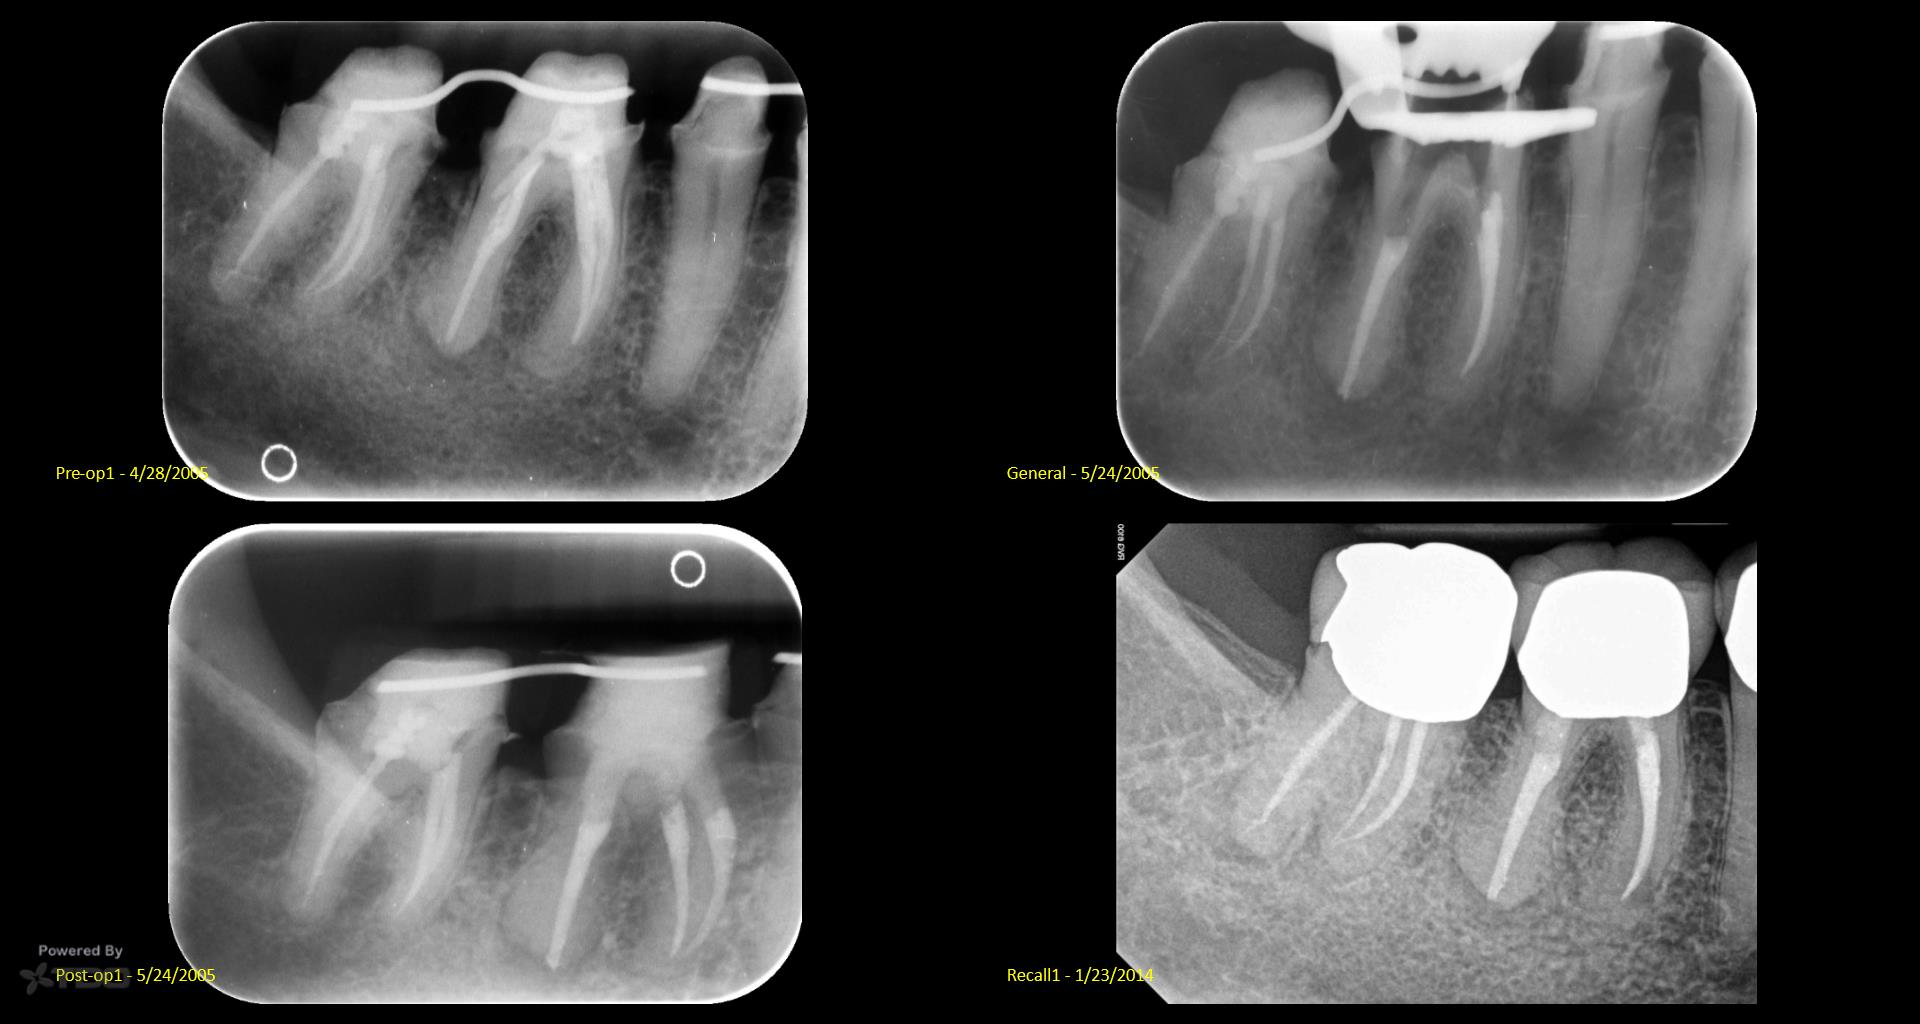

I did a retreat #19 15 years ago. Today symptom free but #18 looks suspicious and maybe even #19……. Perfect case for monitoring….not anxious to do another retreat… gbc

My experience with retreat #19 fifteen years ago was transformative, and I’m grateful to be symptom-free today. However, I’ve noticed convalescent hospital some concerning signs with #18 and possibly #19, which makes me cautious. While I appreciate the value of retreats, I’m not eager to dive back in just yet. Monitoring feels essential now.